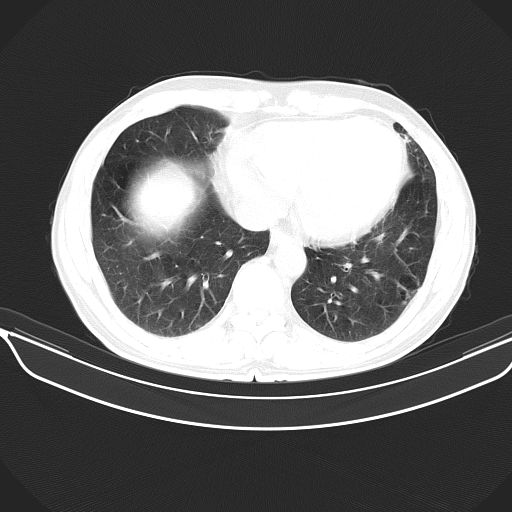

以下是引用心路寻觅在2010-3-1 10:23:00的发言:[br]1、考虑左肺上叶周围型肺癌[br]2、右上肺陈旧性病灶。[br][br][本贴已被 心路寻觅 于 2010-3-1 10:40:18 修改过]

以下是引用shuiyuan在2010-3-1 10:45:00的发言:[br]考虑左肺上叶中心型肺癌伴阻塞型炎症,邻近胸膜受侵。